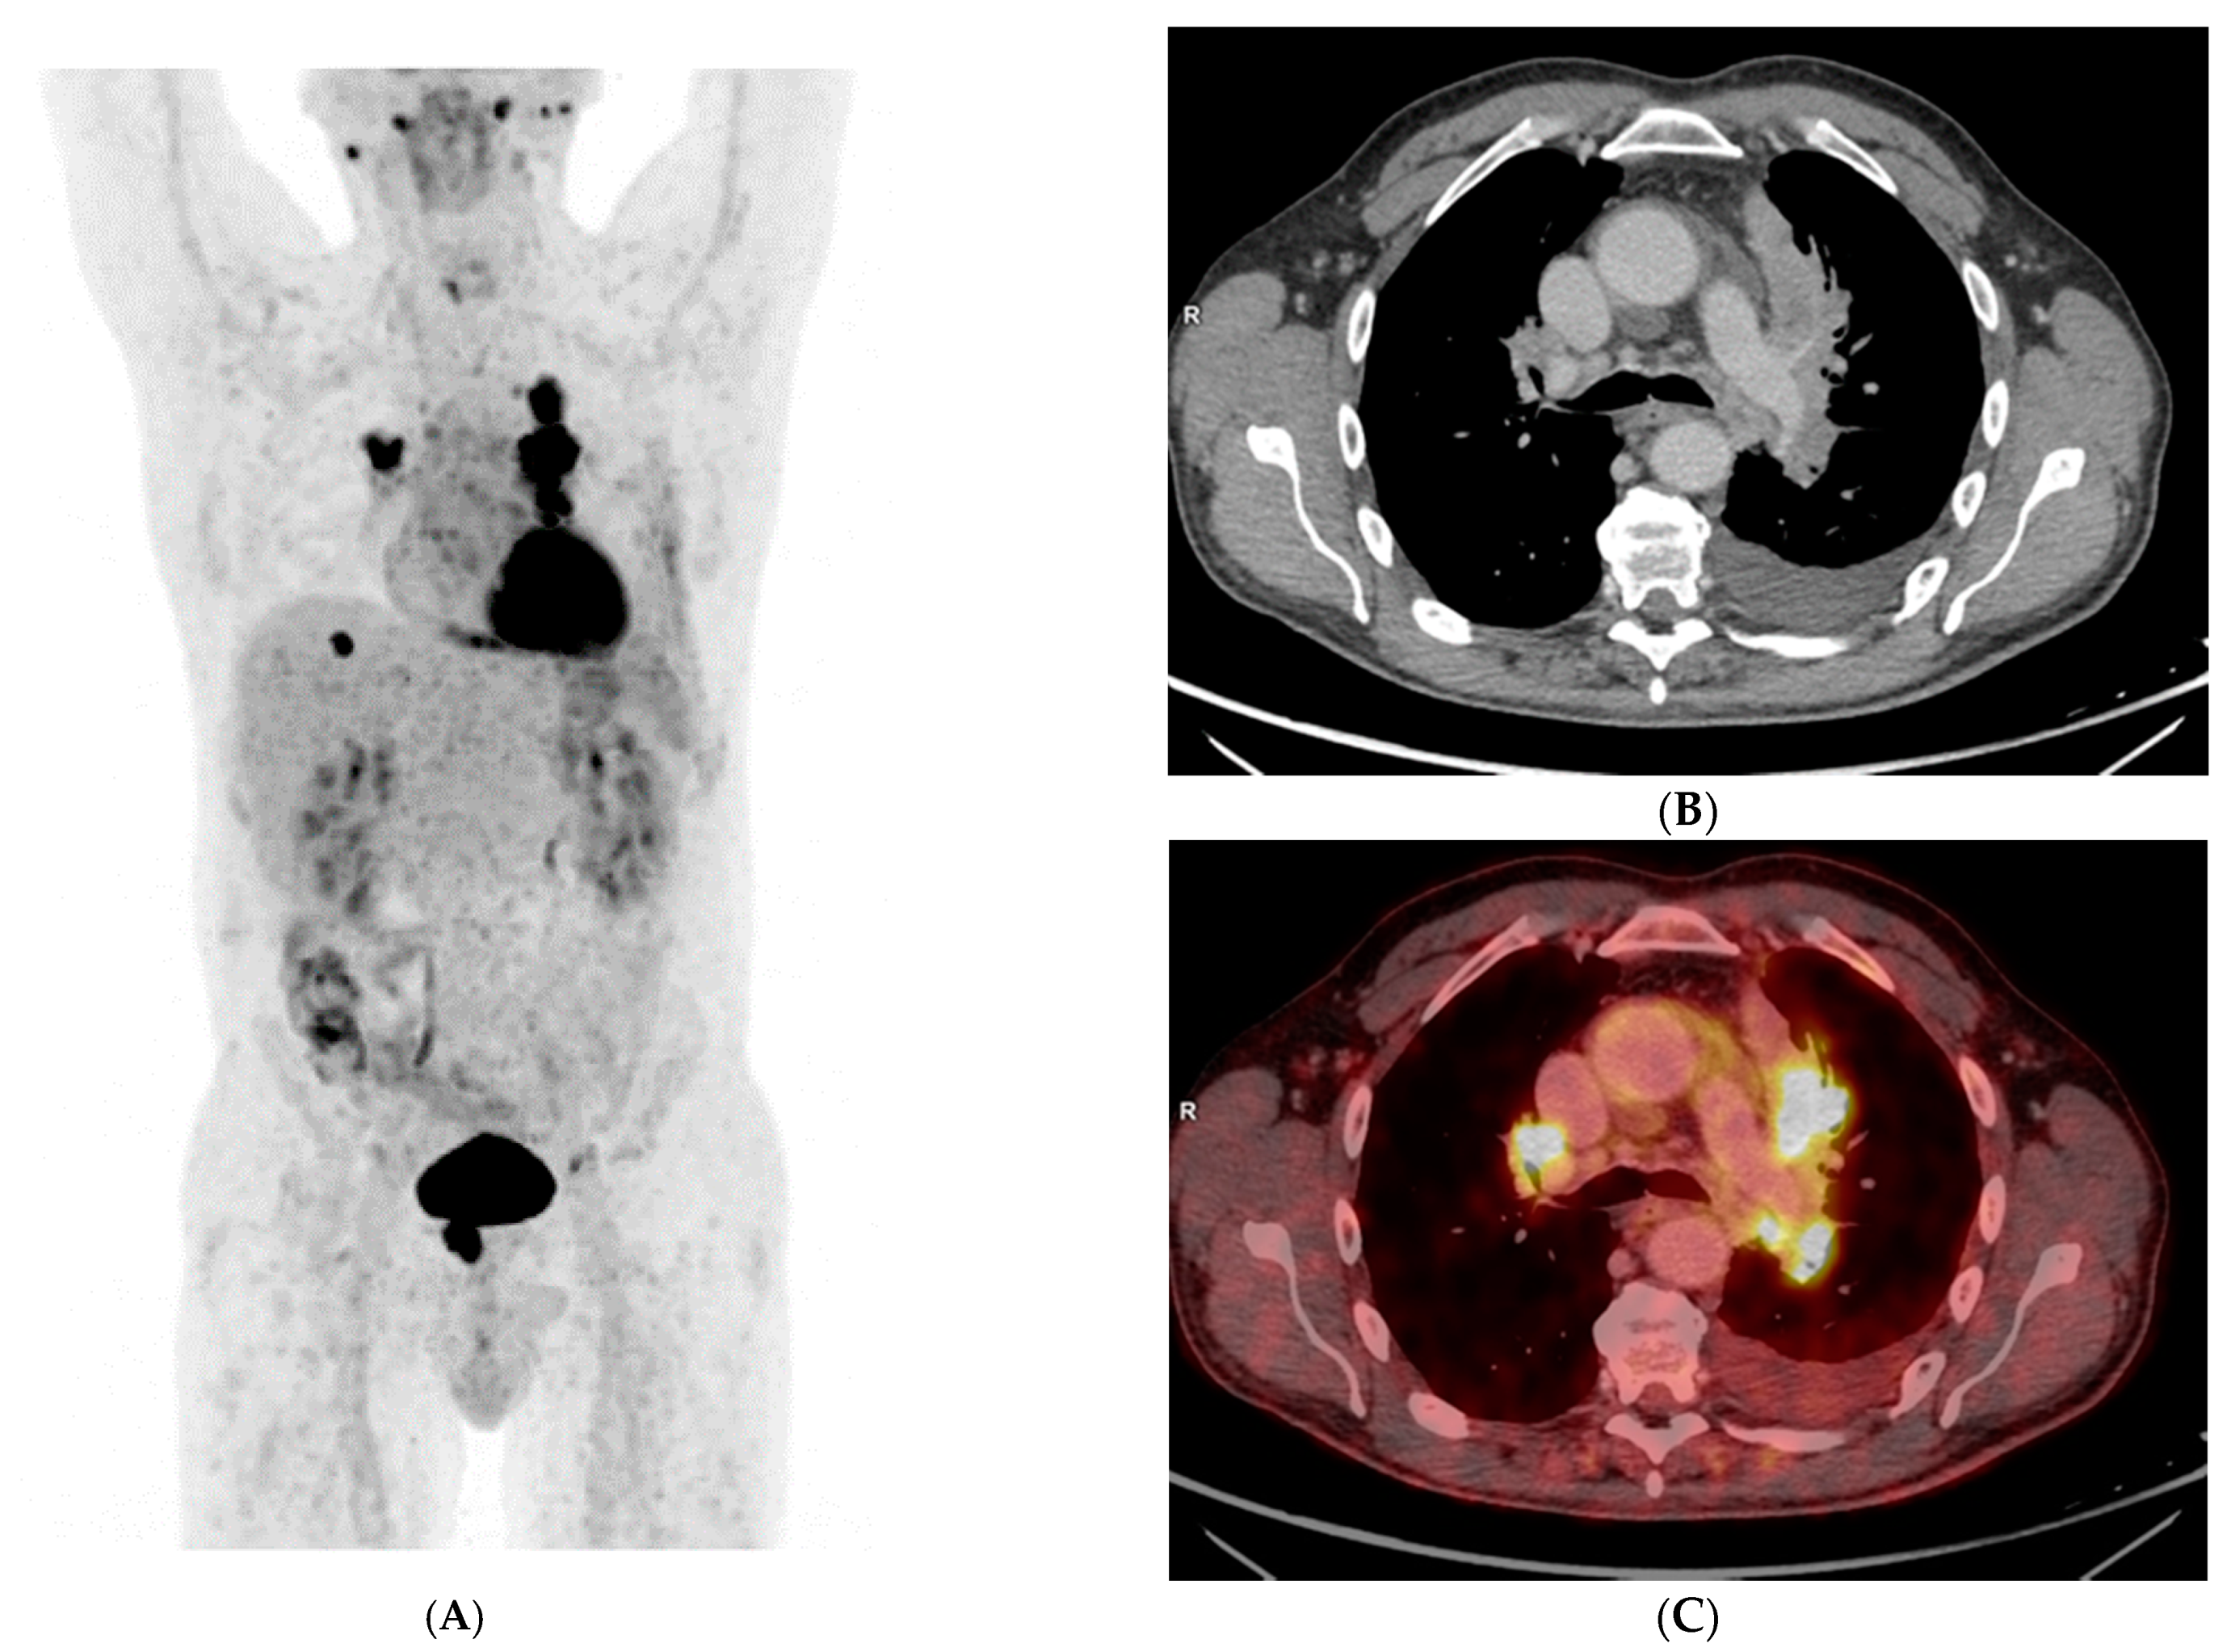

Uncommon Presentation of Granulomatosis with Polyangiitis Mimicking Metastatic Lung Cancer